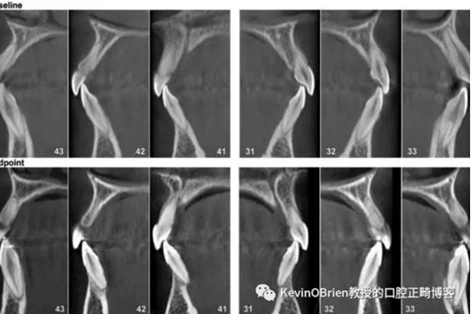

我們都熟悉正畸誘導(dǎo)性牙根吸收(Orthodontically Induced Root Resorption, OIRR)。一些研究把牙根吸收量與幾個(gè)可能原因聯(lián)系了起來(lái),例如治療持續(xù)時(shí)間,矯治器類(lèi)型以及施加的力。雖然這些研究給我們提供了有用的信息,但其大多數(shù)都采用了2D的頭顱側(cè)位X線片。CBCT影像的出現(xiàn)使得對(duì)OIRR的更精確測(cè)量成為可能。因此,作者們做了一項(xiàng)新的研究去探究這個(gè)問(wèn)題:

“用CBCT成像測(cè)量的OIRR的平均值是多少?”

總之,我覺(jué)得我們能慎重地得出結(jié)論:當(dāng)使用CBCT測(cè)量OIRR時(shí),吸收的平均值是0.6-0.8mm。這是一個(gè)令人安心的小值。